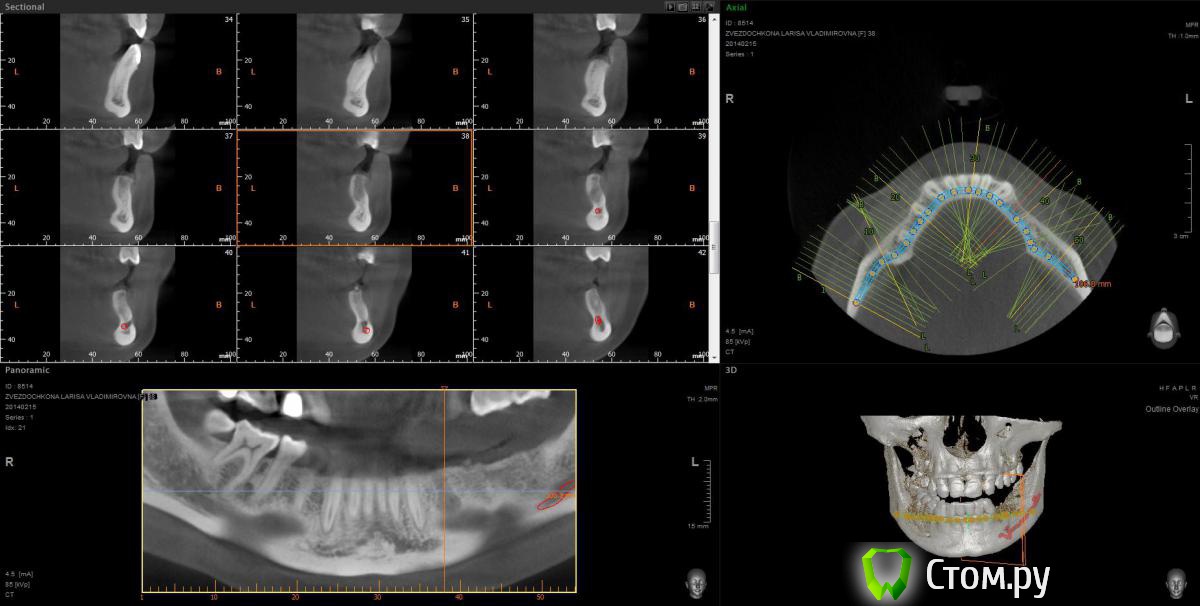

mapmax Опубликовано 3 марта, 2014 Поделиться Опубликовано 3 марта, 2014 Итак,коллеги,нуждаюсь в Вашем совете. У пациентки концевой дефект в обл 34 35 36 37, в периапикальной обл. 34 был воспалительный процесс который обострился и осенью прошлого года зуб был удален(не мной). Сейчас стоим перед имплантацией. Я рекомендую ставить импланты в обл отсутствующих зубов,но по финансовым соображениям пациентка настаивает на операции в обл 34 35 и позже в обл 36 37. Система выбрана Штрауманн SP SLActiv. Из за особенностей формы альвеолярного отростка в обл. 34 35( S-образная) и недавнего удаления 34 я рассматриваю установку импланта с язычным наклоном размера 4.8х10 RN в обл 35 RN 4.8х12. Но есть опасность оголения витков с вестибулярной стороны.Может все же сперва провести аугментацию "Аллопластом" с мембраной с вестибулярной стороны и отсрочено имплантация?! Срезы ДКТ прилагаю. Спасибо. Ссылка на комментарий